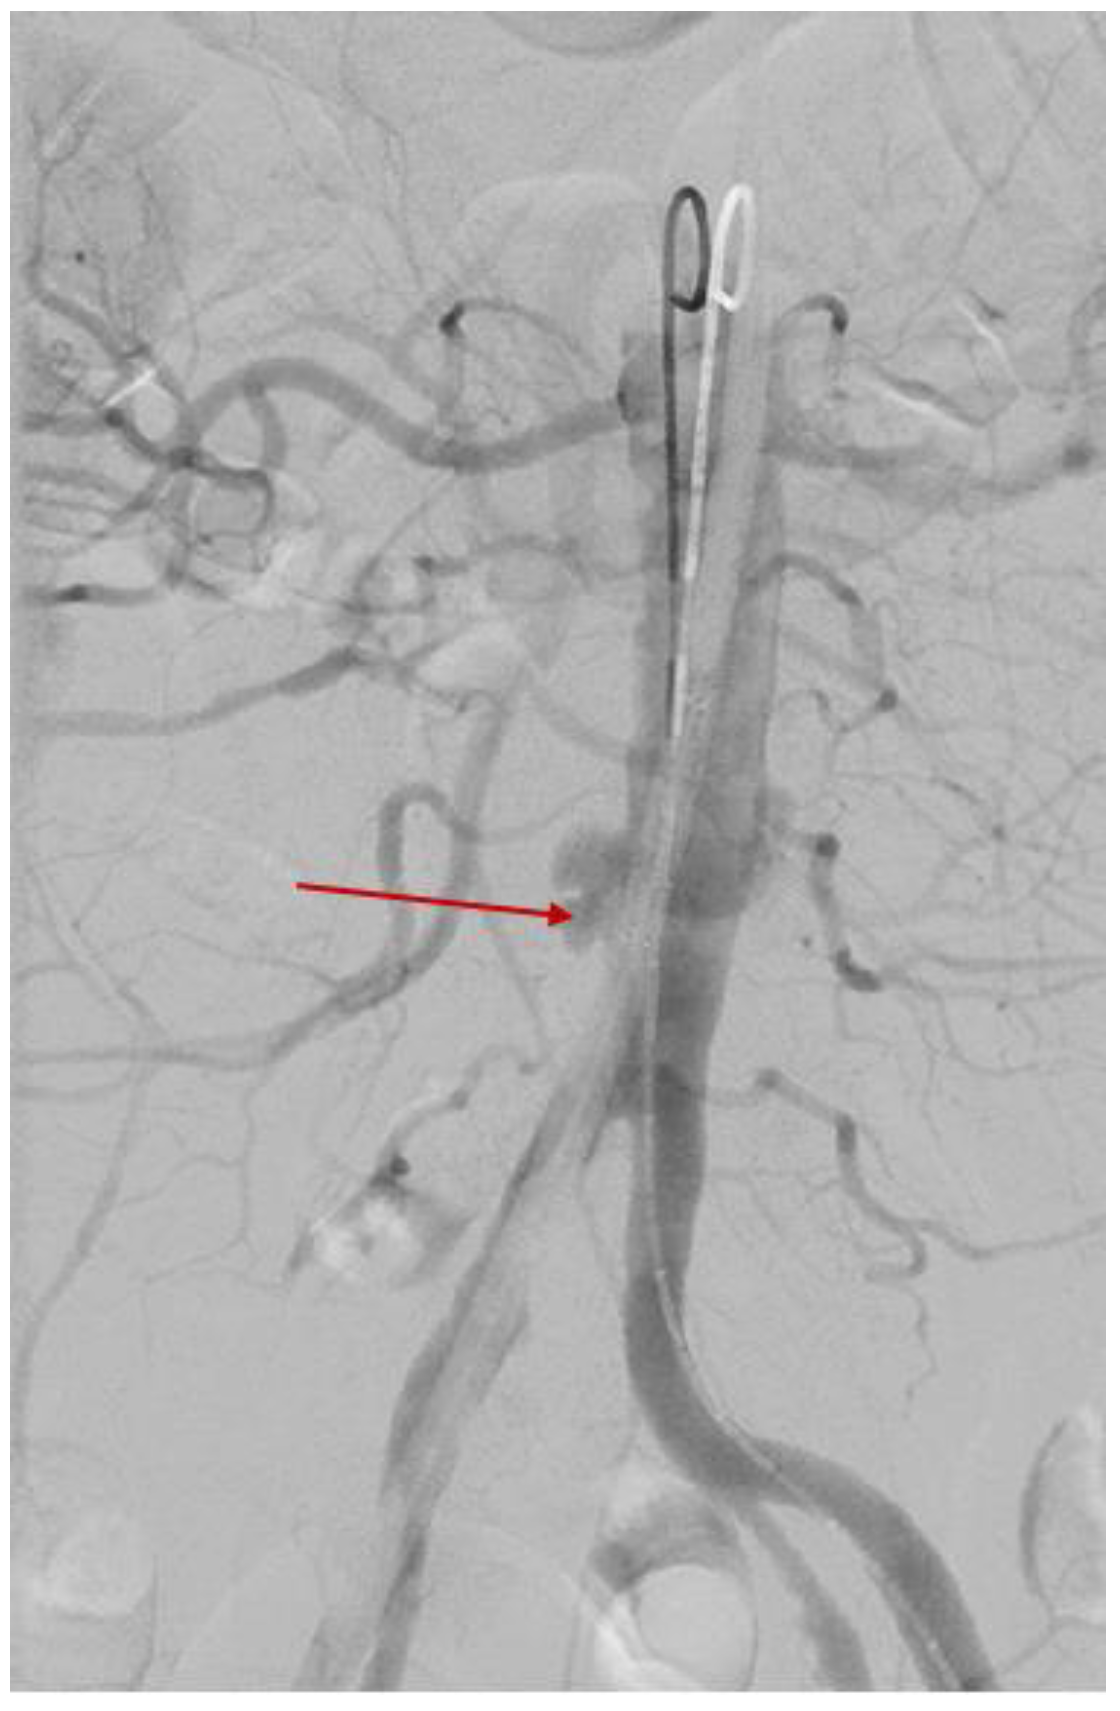

3.2.4. Minimally Invasive Surgery

3.2.5. One-Month Post-Surgery Follow-Up